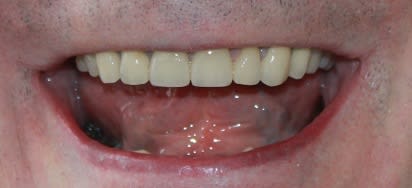

J'avais eu un boulot comme ça, probablement, le plus compliqué que j'ai jamais eu à gérer, les dents à ras la gencive genre attaque chimique interdite par la convention de Genève, et dv parfaitement conservée. Les incisives mandibulaires avaient fini à la benne pour faire de la place.

Je jette un oeil pour voir si je retrouve les photos.

Edit: a y est j'ai retrouvé. Même l'endo avait été une chierie sans nom, toutes calcifiées, toutes les mono-radiculées avaient 2 canaux distincts, j'avais perforé la 45 en tirant de travers...

Img 4061 ru6pto - Eugenol

Boooo .on reconnait ta signature , tu avais posté un meme genre de sourire dans :

"Le boulot dont vous etes fier" , ou 1 truc comme ça .

04/04/2018 à 00h19

Ce boulot date de 2 ans je crois. Pas retrouvé celui auquel tu penses, mais j'imagine que ça doit plus être le style du prothésiste que le mien.

J'y ai pensé parce que j'ai revu le patient aujourd'hui, je m'occupe de son épouse maintenant. Stellites en place depuis 23 ans, "un peu" enfoncés. Donc vestibulo version des antérieures restantes bien sûr. C'est plus simple, elle j'ai pu lui remonter sa dv haha.